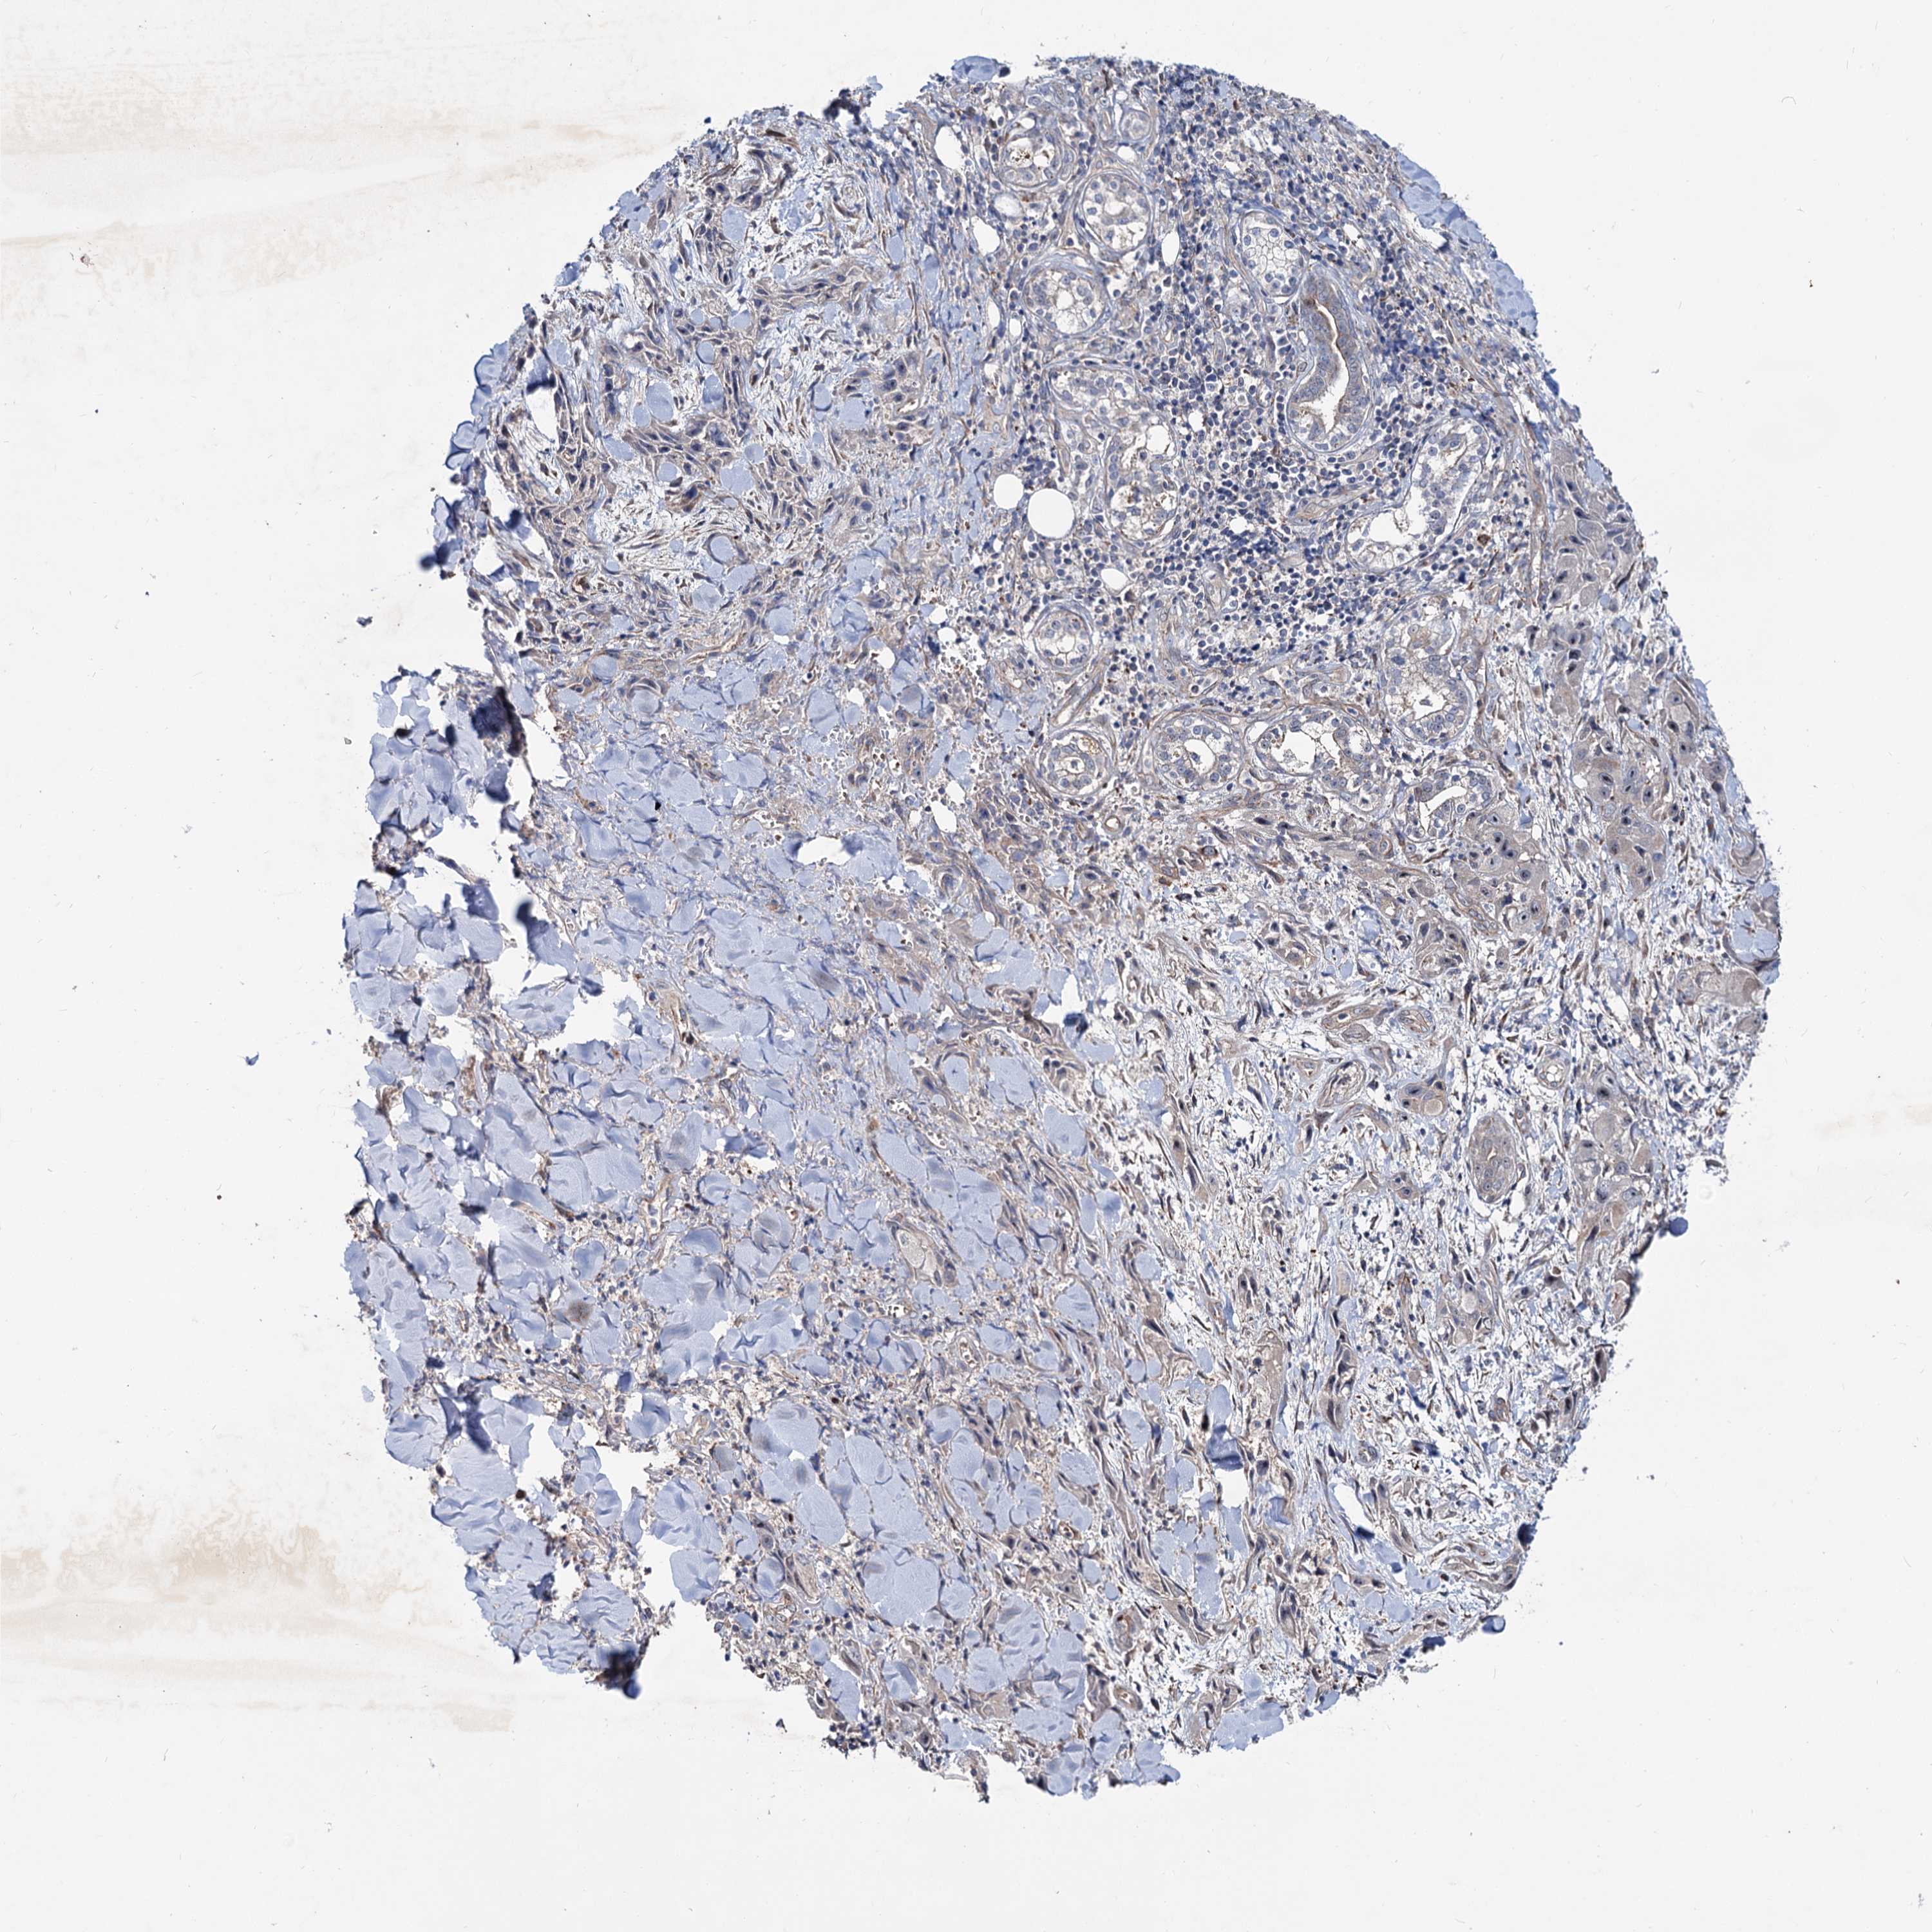

SKIN CANCER - Protein expressioni

A mouse-over function shows sample information and annotation data. Click on an image to view it in a full screen mode. Samples can be filtered based on level of antibody staining by selecting one or several of the following categories: high, medium, low and not detected. The assay and annotation is described here.

Antibody stainingi

Antibody staining in the annotated cell types in the current human tissue is reported as not detected, low, medium, or high, based on conventional immunohistochemistry profiling in selected tissues. This score is based on the combination of the staining intensity and fraction of stained cells.

Each image is clickable and will lead to virtual microscopy that enables deeper exploration of all samples and also displays staining intensity scores, fraction scores and subcellular localization as well as patient and tissue information for each sample.

Antibody HPA038929

Squamous cell carcinoma, NOS